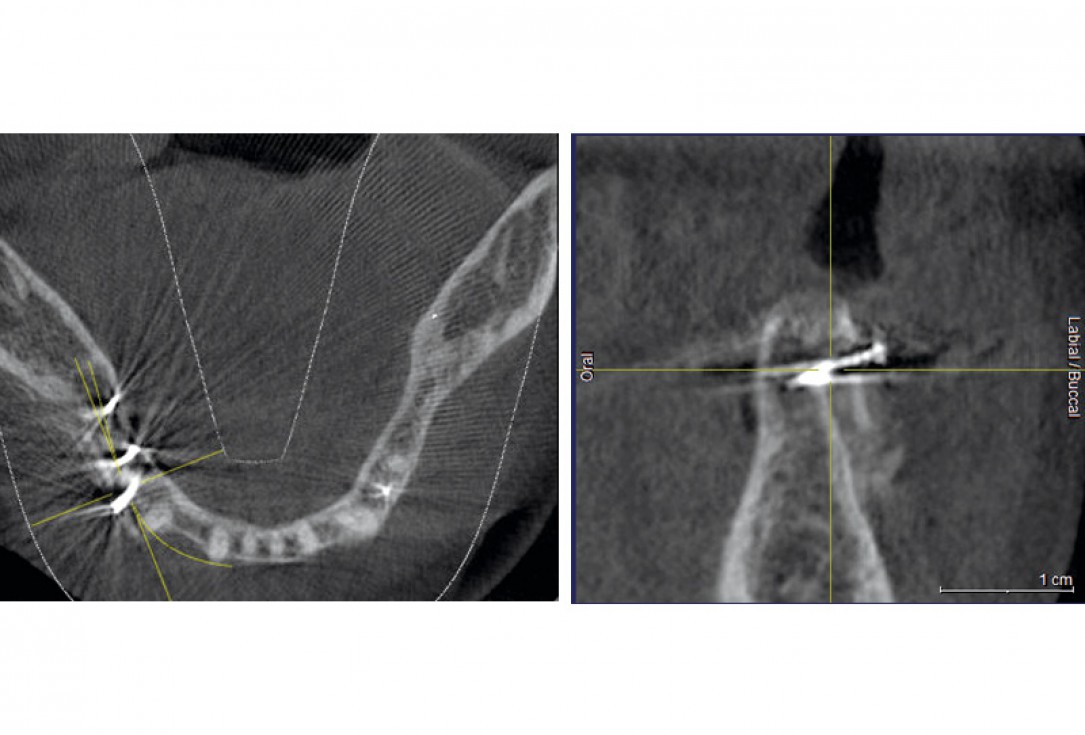

08 / 20 - CBCT recording after the augmentation shows the cortical plate about 3 to 4 mm distant from the host boneHorizontal ridge augmentation with maxgraft® cortico - M.Sc. E. Kapogianni

16 / 20 - CBCT after the implantation shows position of the implant within vital bone tissue and the adjacent allogenic cortical plateHorizontal ridge augmentation with maxgraft® cortico - M.Sc. E. Kapogianni